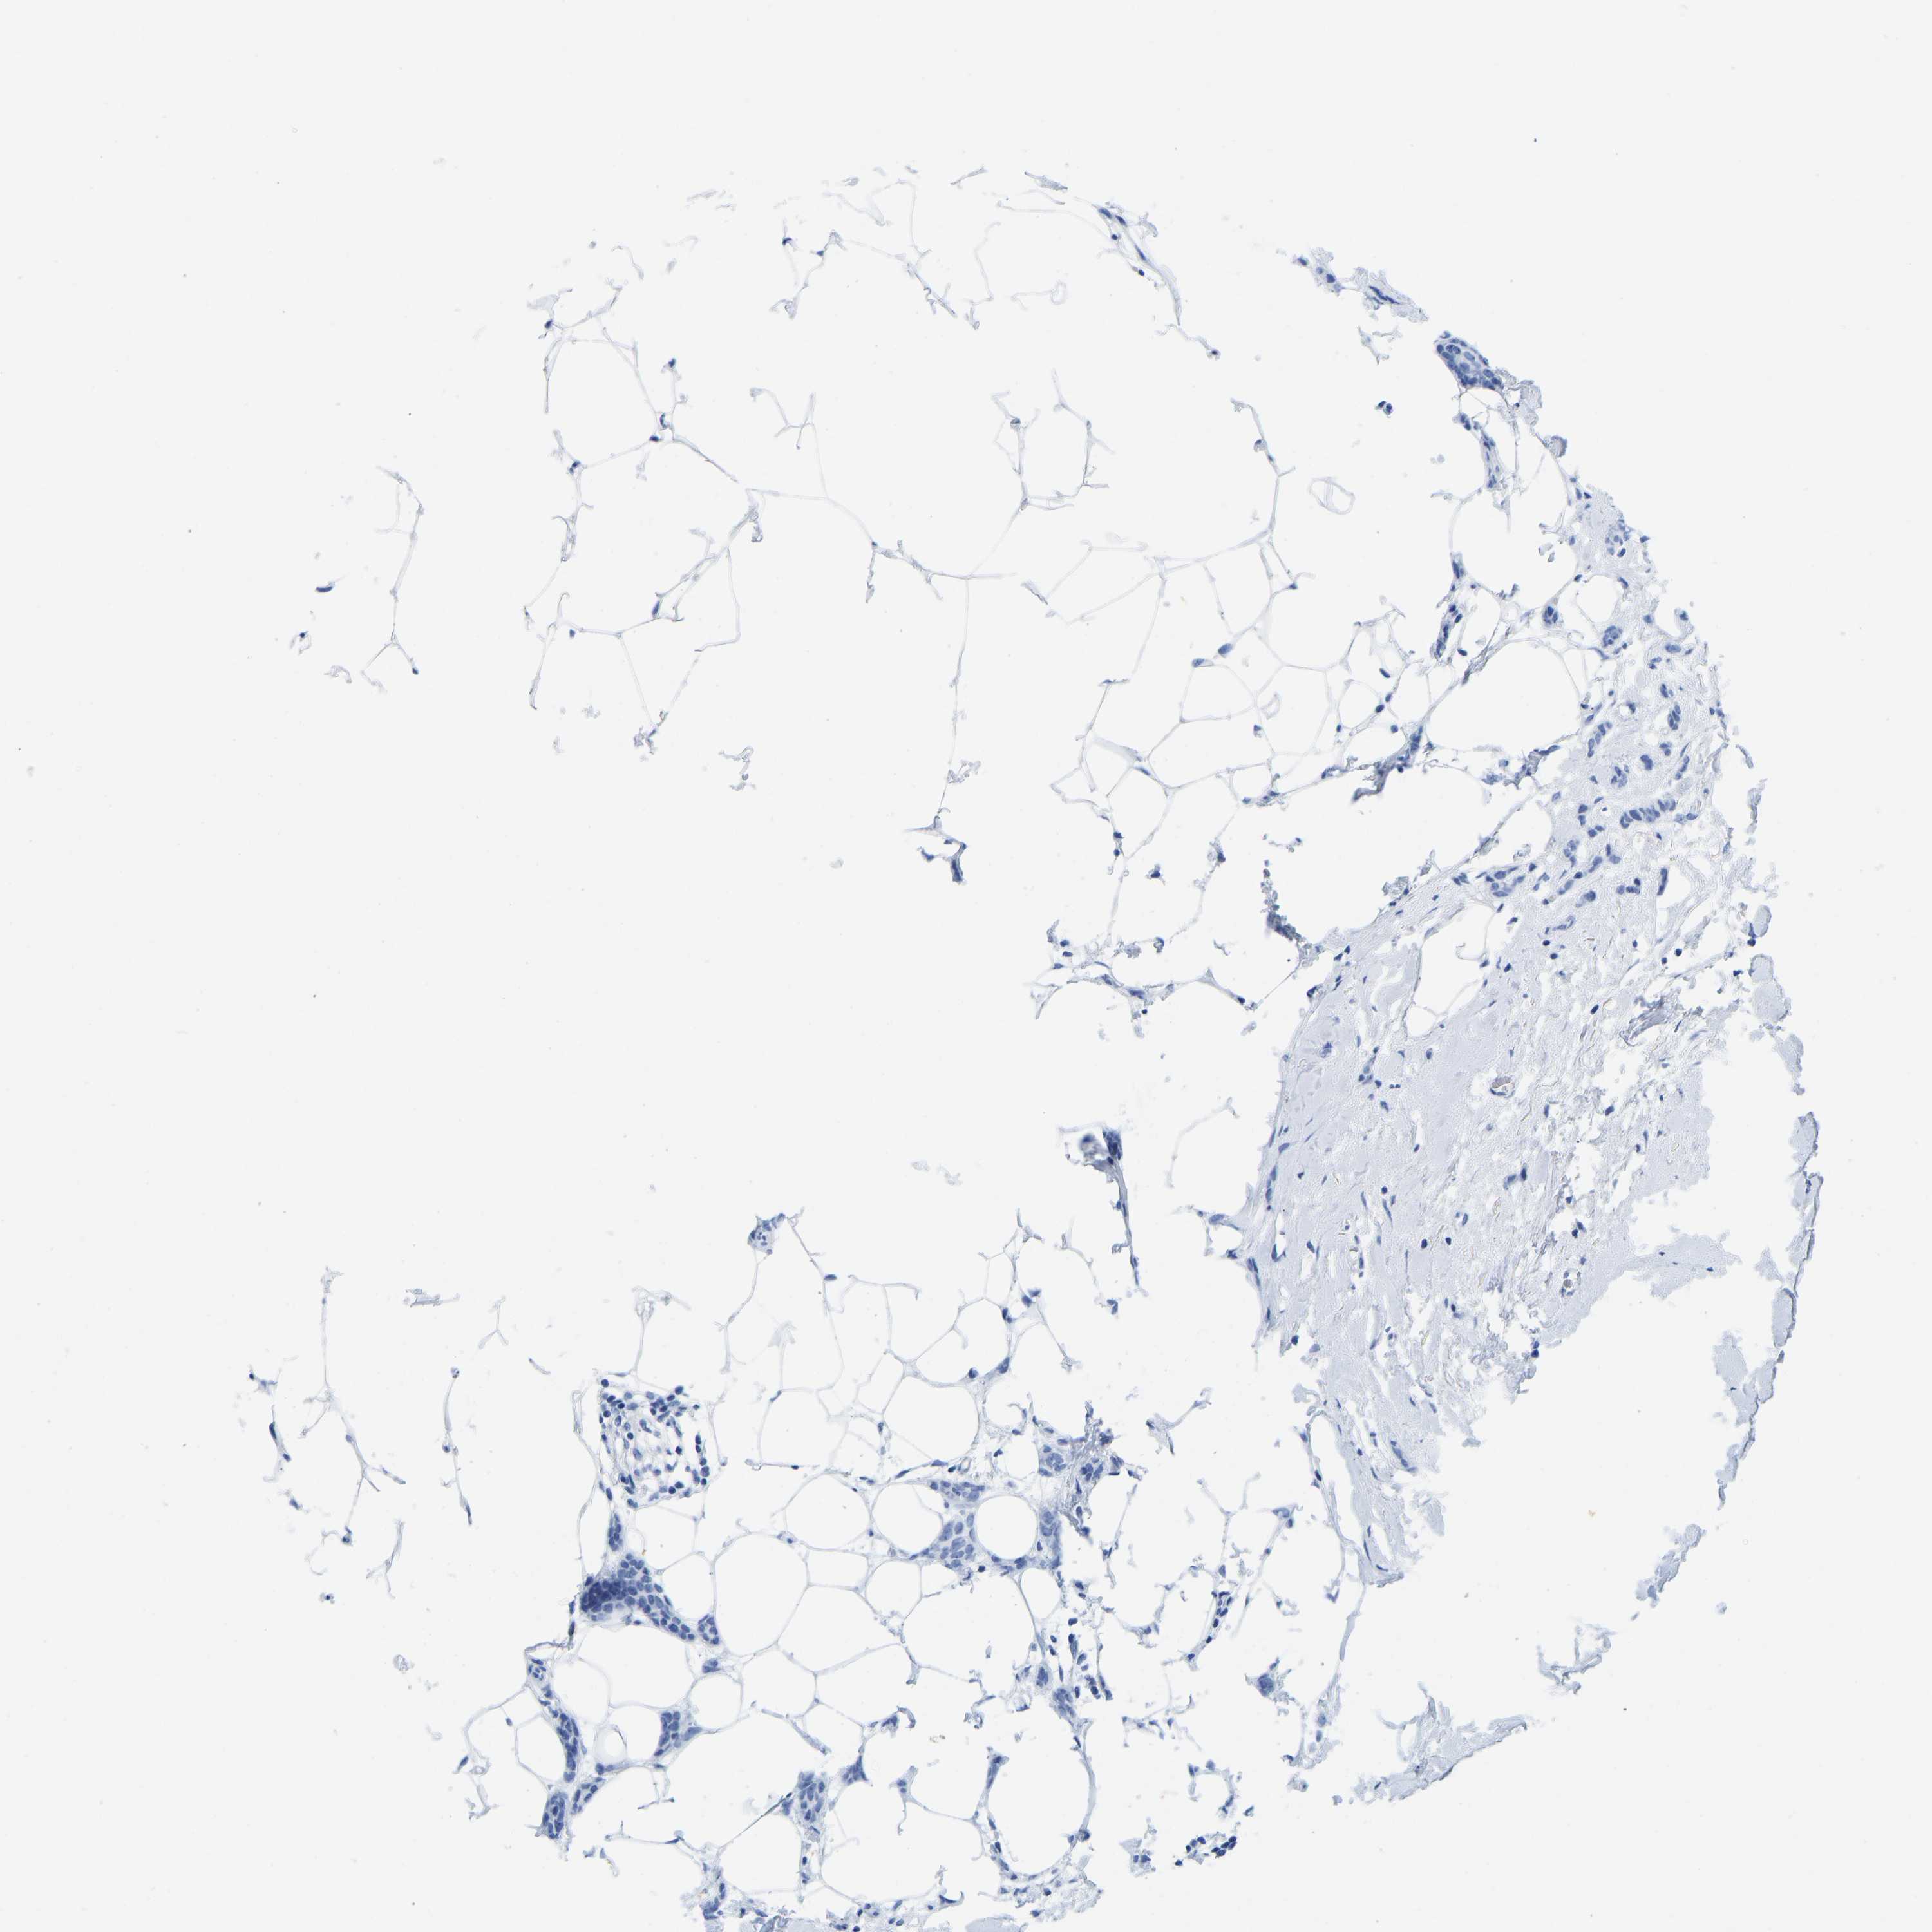

CANCER BREAST CANCER Show tissue menu

BRCA TCGA BRCA VALIDATION PROTEIN EXPRESSION